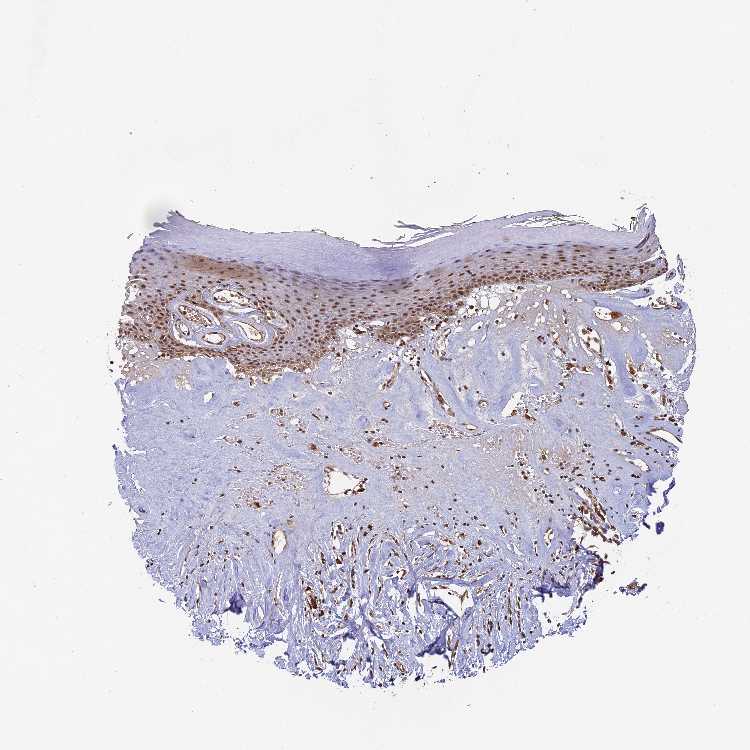

TISSUE PRIMARY DATA SKIN Show tissue menu

SKIN 1 - Antibody stainingi

Antibody staining in the annotated cell types in the current human tissue is reported as not detected, low, medium, or high, based on conventional immunohistochemistry profiling in selected tissues. This score is based on the combination of the staining intensity and fraction of stained cells.

Each image is clickable and will lead to virtual microscopy that enables deeper exploration of all samples and also displays staining intensity scores, fraction scores and subcellular localization as well as patient and tissue information for each sample.

Antibody HPA040959Antibody HPA043401

Langerhans -Medium

Cells in basal layer Medium-

Cells in corneal layer Not detected-

Cells in granular layer Medium-

Cells in spinous layer Medium-

Endothelial cells Medium-

Extracellular matrix Not detected-

Fibroblasts -Medium

Fibrohistiocytic cells High-

Keratinocytes -Low

Langerhans cells Medium-

Lymphocytes High-

Melanocytes HighMedium

Vascular mural cells Not detected-